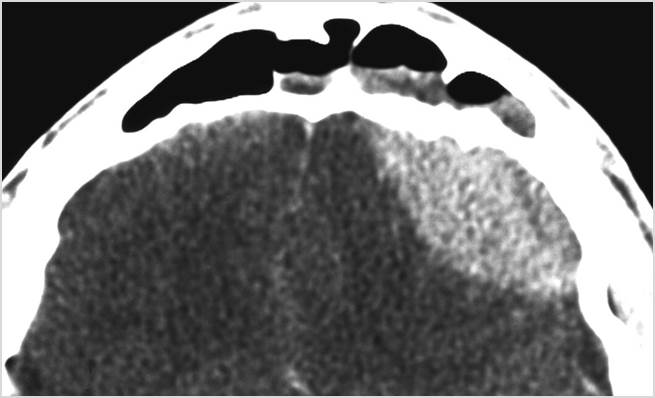

Intracranial

There is brain edema specifically involving the frontal and temporal lobes. [Yes/No]

There is cerebritis specifically involving the frontal and temporal lobes. [Yes/No]

There is brain abscess specifically involving the frontal and temporal lobes. [Yes/No]

There is likely meningitis, meningoencephalitis with complicating hydrocephalus or brain herniation. [Yes/No]